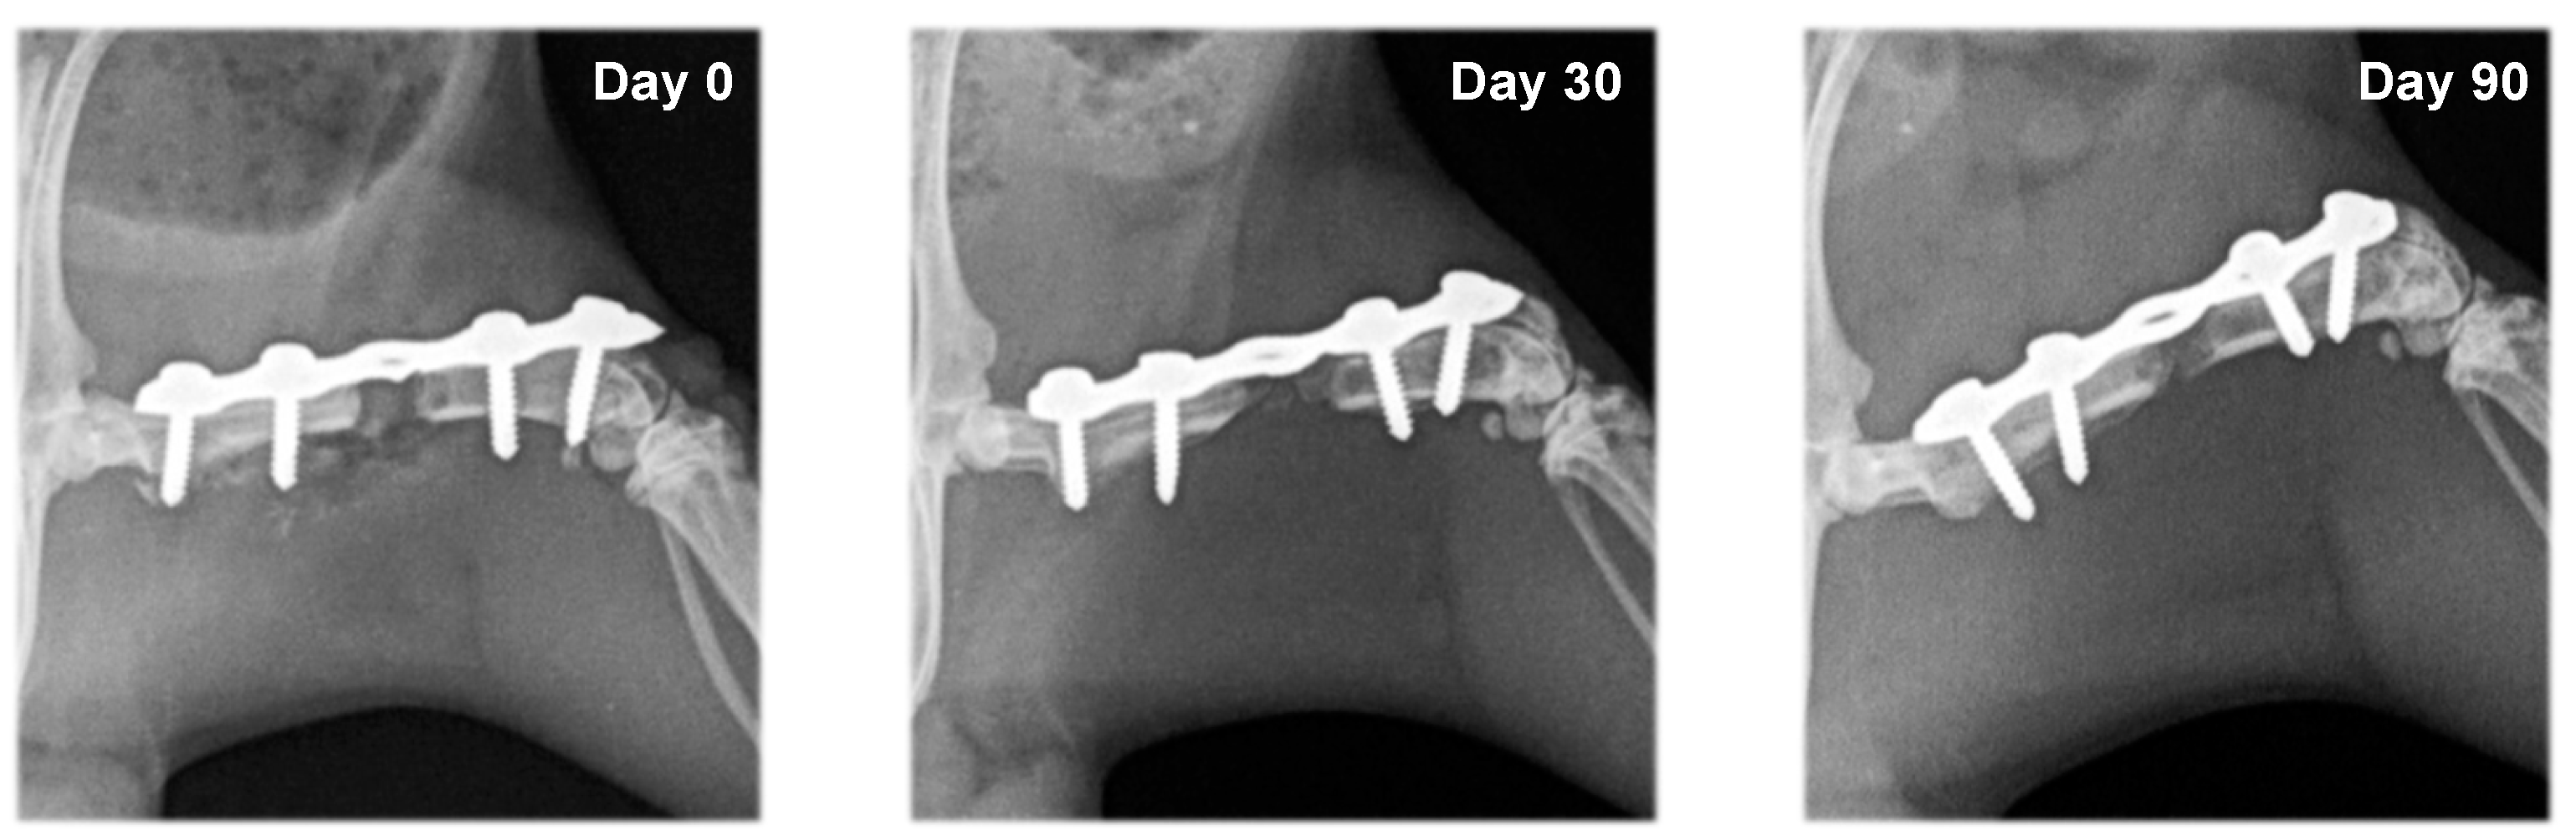

3.2. Radiography